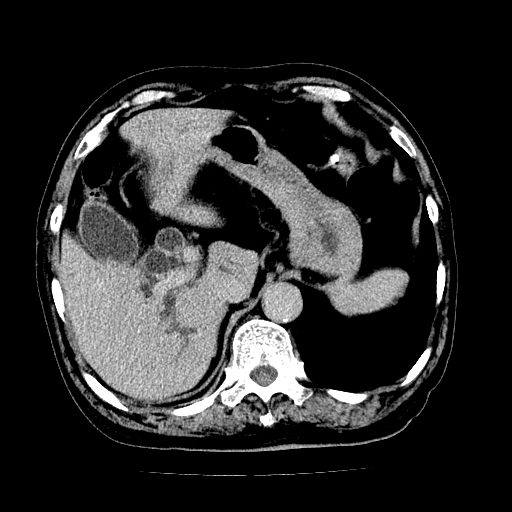

男,71岁,皮肤黄染四天。

肝内外胆管及胆总管上段扩张,考虑为梗阻所致,建议mrcp检查。

考虑胆总管癌并肝内外胆管扩张。

支持考虑胆总管癌并肝内外胆管扩张。 局部应薄扫。心包钙化。

胰腺上端胆总管内见软组织影,强化不明显,结合临床,还是考虑低位梗阻性黄疸,胆总管癌可能性大